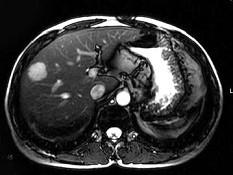

问题 男,42岁。体检B超发现肝内占位,行MRI检查见肝右叶长T1长T2异常信号。依据MRI图应诊断为 ( )

选项 A、肝脏单发转移瘤 B、未见异常 C、肝血管瘤 D、肝癌 E、肝囊肿

答案 C